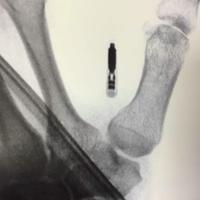

一名患者因摔伤肘部至医院就诊,接下来的治

一名患者因摔伤肘部至医院就诊,接下来的治疗是什么?...

由 medjpg 发表于 2026-03-24 22:32